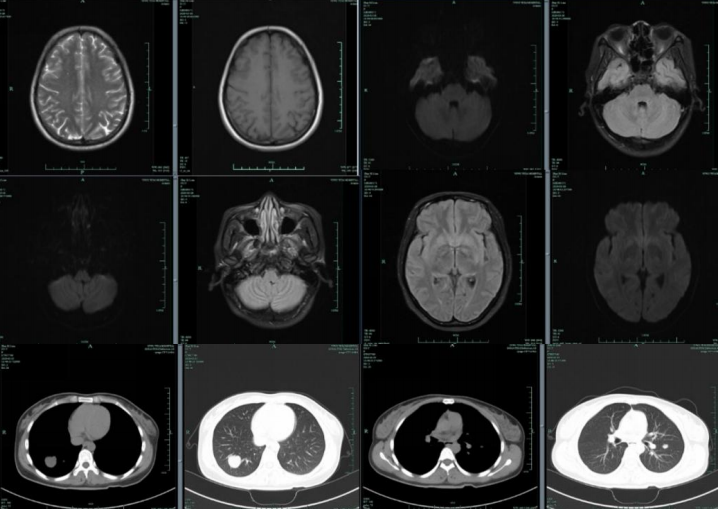

患者男,52岁,因“幻觉胡言 乱语3天,伴视物重影2天”入院。

答案:韦尼克脑病。易受到硫胺素(维生素B1)缺乏造成的损害的部位包括丘脑、乳头体、导水管周围和室旁区域、蓝斑、 颅神经核和网状结构。临床表现包括以下三个症状:眼肌麻痹、共济失调和脑病症状精神状态或智能状态改变。